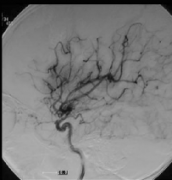

烟雾病图片(烟雾病手术过程图片)

烟雾病手术过程图片 烟雾病图片 3大烟雾病危害 1、短暂性脑缺血发作 短暂性脑缺血一般由于颈内动脉末端、大脑前动脉、大脑中动脉,有时也包括大脑后...